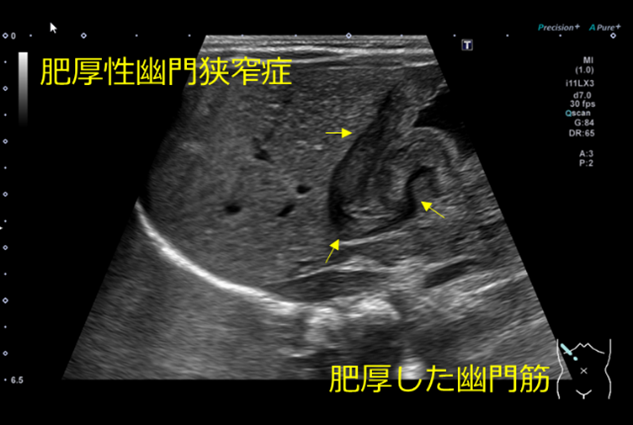

肥厚性幽門狭窄症とは

胃幽門部輪状筋の肥厚により幽門管が狭小化し、胃内容の通過障害をきたす状態のことです。

生後1ヵ月頃から、非胆汁性の噴水状嘔吐を繰り返します。